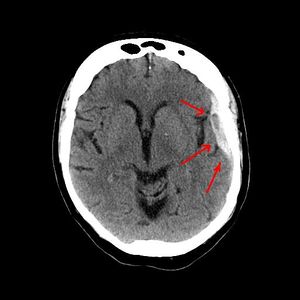

يعتمد رئيساً على تصوير الدماغ (التصوير الطبقي المحوري والرنين المغنطيسي MRI)، وفيه يظهر النزف عادة على شكل تجمع هلالي بين الجمجمة والدماغ.